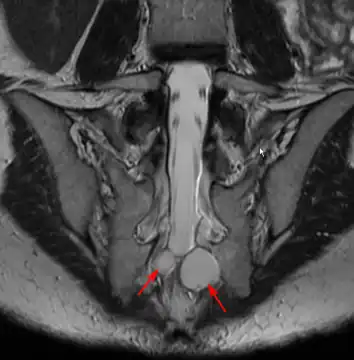

Tarlov cysts are relatively uncommon when compared to other neurological cysts. Initially, Isadore Tarlov believed them to be asymptomatic, however as his research progressed, Tarlov found them to be symptomatic in a number of patients. These cysts are often detected incidentally during MRI or CT scans for other medical conditions. They are also observed using magnetic resonance neurography with communicating subarachnoid cysts of the spinal meninges. Cysts with diameters of 1 cm or larger are more likely to be symptomatic; although cysts of any size may be symptomatic dependent on location and etiology. Some 40% of patients with symptomatic Tarlov cysts can associate a history of trauma or childbirth.[4] Current treatment options include CSF aspiration, fibrin-glue therapy, laminectomy with wrapping of the cyst, among other surgical treatment approaches. Interventional treatment of Tarlov cysts is the only means by which symptoms might permanently be resolved due to the fact that the cysts often refill after aspiration. Tarlov cysts often enlarge over time, especially if the sac has a check valve type opening. They are differentiated from other meningeal and arachnoid cysts because they are innervated and diagnosis can in cases be demonstrated with subarachnoid communication.

Although they are most frequently reported along sacral regions, they are rarely seen in other locations along the spine.[6] Women are more likely to exhibit symptoms [7][8] They can also appear in clusters or bilaterally along the spine, thus symptoms can be unilateral, bilateral, or with symptoms more dominant on one side. The cases of reported symptomatic Tarlov cysts ranges from 15% to 30% of the overall reported Tarlov cyst case, depending on the source of literature. Nevertheless, these cysts are important clinical entities because of their tendency to increase in size over time, potentially causing complications and eroding the surrounding bone tissue.[9][10][11] Patients with symptomatic Tarlov cysts near the sacrum (and not other locations of the spine) can be divided into 4 categories, according to their experienced symptoms:[12]

Tarlov cysts are most commonly located in the S1 to S4/S5 region of the spinal canal, but can be found along any region of the spine. They usually form on the extradural components of sacrococcygeal nerve roots at the junction of dorsal root ganglion and posterior nerve roots and arise between the endoneurium and perineurium.[17] Occasionally, these cysts are observed in the lumbar and thoracic spine.[14] However, these cysts most commonly arise at the S2 or S3 junction of the dorsal nerve root ganglion.[9][22] The cysts are often multiple, extending around the circumference of the nerve, and can enlarge over time to compress neighboring nerve roots, to cause bone erosion.[10] The cysts may be found anterior to the sacral area and have been known to extend into the abdominal cavity. These cysts, though rare, can be found to grow large - over 3–4 centimetres (1.2–1.6 in) in size, often causing severe abdominal pain from compression on the cyst itself as well as adjoining nerves.

MRI

MRI, or Magnetic Resonance Imaging, is considered the imaging study of choice in identifying Tarlov cysts. MRI provides better resolution of tissue density, absence of bone interference, multiplanar capabilities, and is noninvasive. Plain films may show bony erosion of the spinal canal or of the sacral foramina. On MRI pictures, the signal is the same as the CSF one.